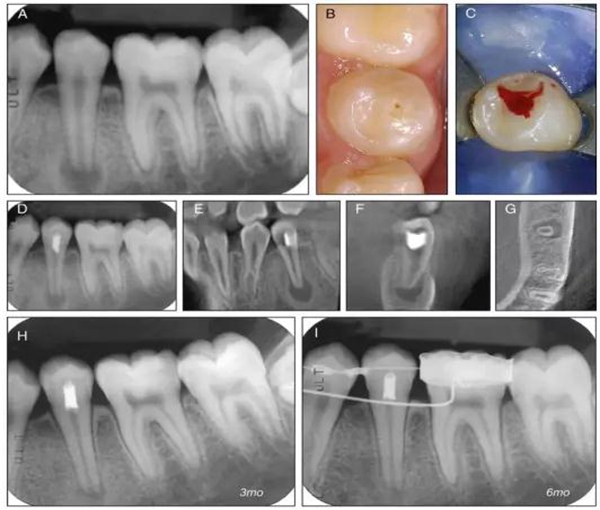

原則上年輕恒牙的牙髓治療應(yīng)盡可能以保存活髓的方式以便不影響牙根繼續(xù)發(fā)育。本文3個(gè)病例均描述了根尖尚未發(fā)育完成的下頜前磨牙被確診為牙髓壞死伴有大面積根尖病損,治療過程中在根管內(nèi)發(fā)現(xiàn)了部分活髓,而采用活髓切斷后都取得了很好的療效。